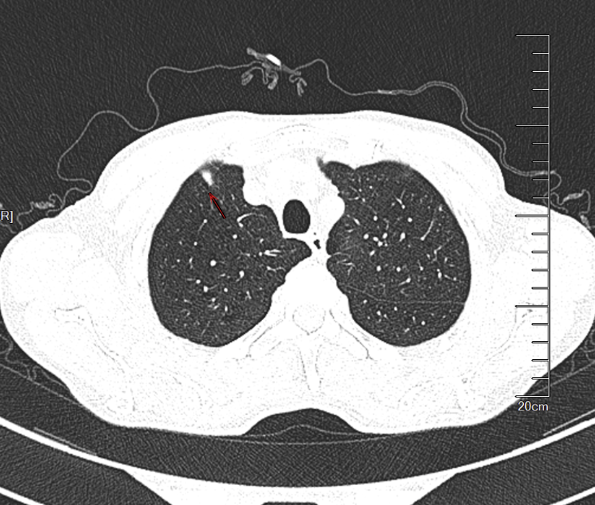

(5)、[2025-06-06]支气管镜(图1)并送检靶向病原微生物高通量测序(tNGS)(图2、图3、图4):如下图:

(6)、我院胸部CT:1、右肺上叶后段磨玻璃结节,密切随诊。(Lung-RADS 3);2、余肺内可见多发微小结节,随诊。(Lung-RADS 2)3、右肺中叶不张。右肺下叶背段少许支扩。4、升主动脉横径增宽,径约41mm。